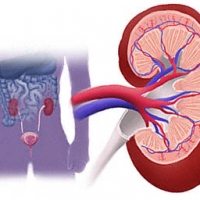

A vizeletbõl anorganikus anyag csapódik ki, amely a kelyhekben, a vesemedencében különbözõ nagyságú és alakú kövekké áll össze. Õsi idõ k óta ismert, igen gyakori bete.....